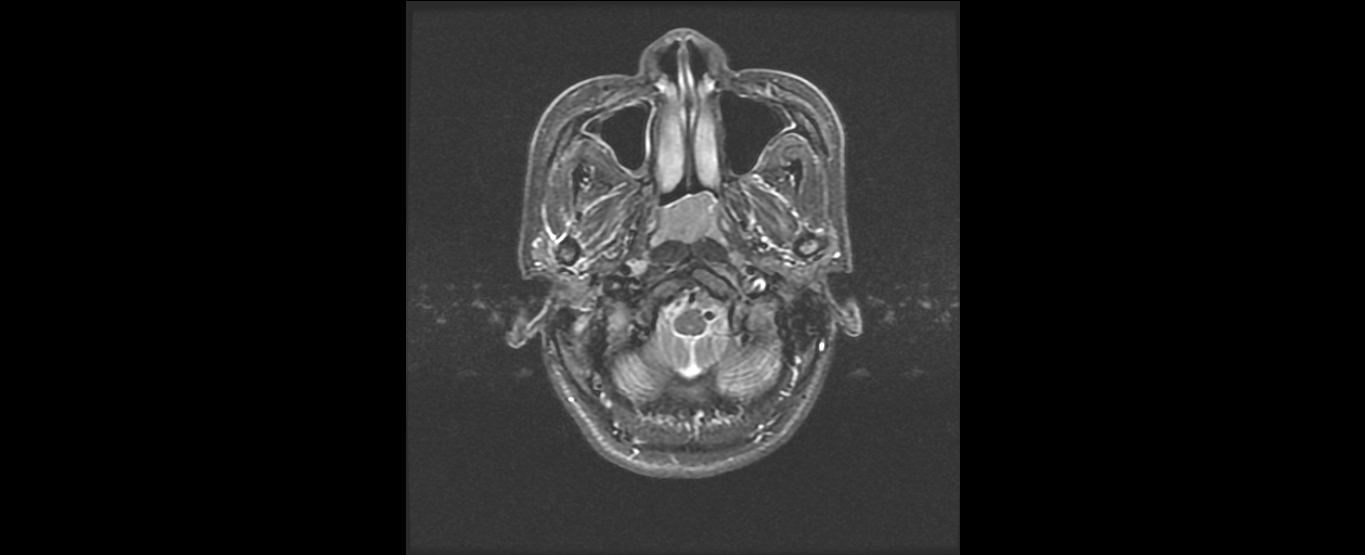

患者韦某某,女,37岁,2016年8月诊断为:鼻咽非角化未分化型癌(T2N2M0 III期),诱导化疗后行鼻咽癌根治性调强放疗,同期顺铂化疗,放疗结束后案辅助化疗。治疗结束复查见患者鼻咽肿物及颈部淋巴结均消退,疗效良好,目前随访1年患者各项检查指标完全恢复正常,已经恢复正常生活和工作。

放疗后鼻咽部MRI